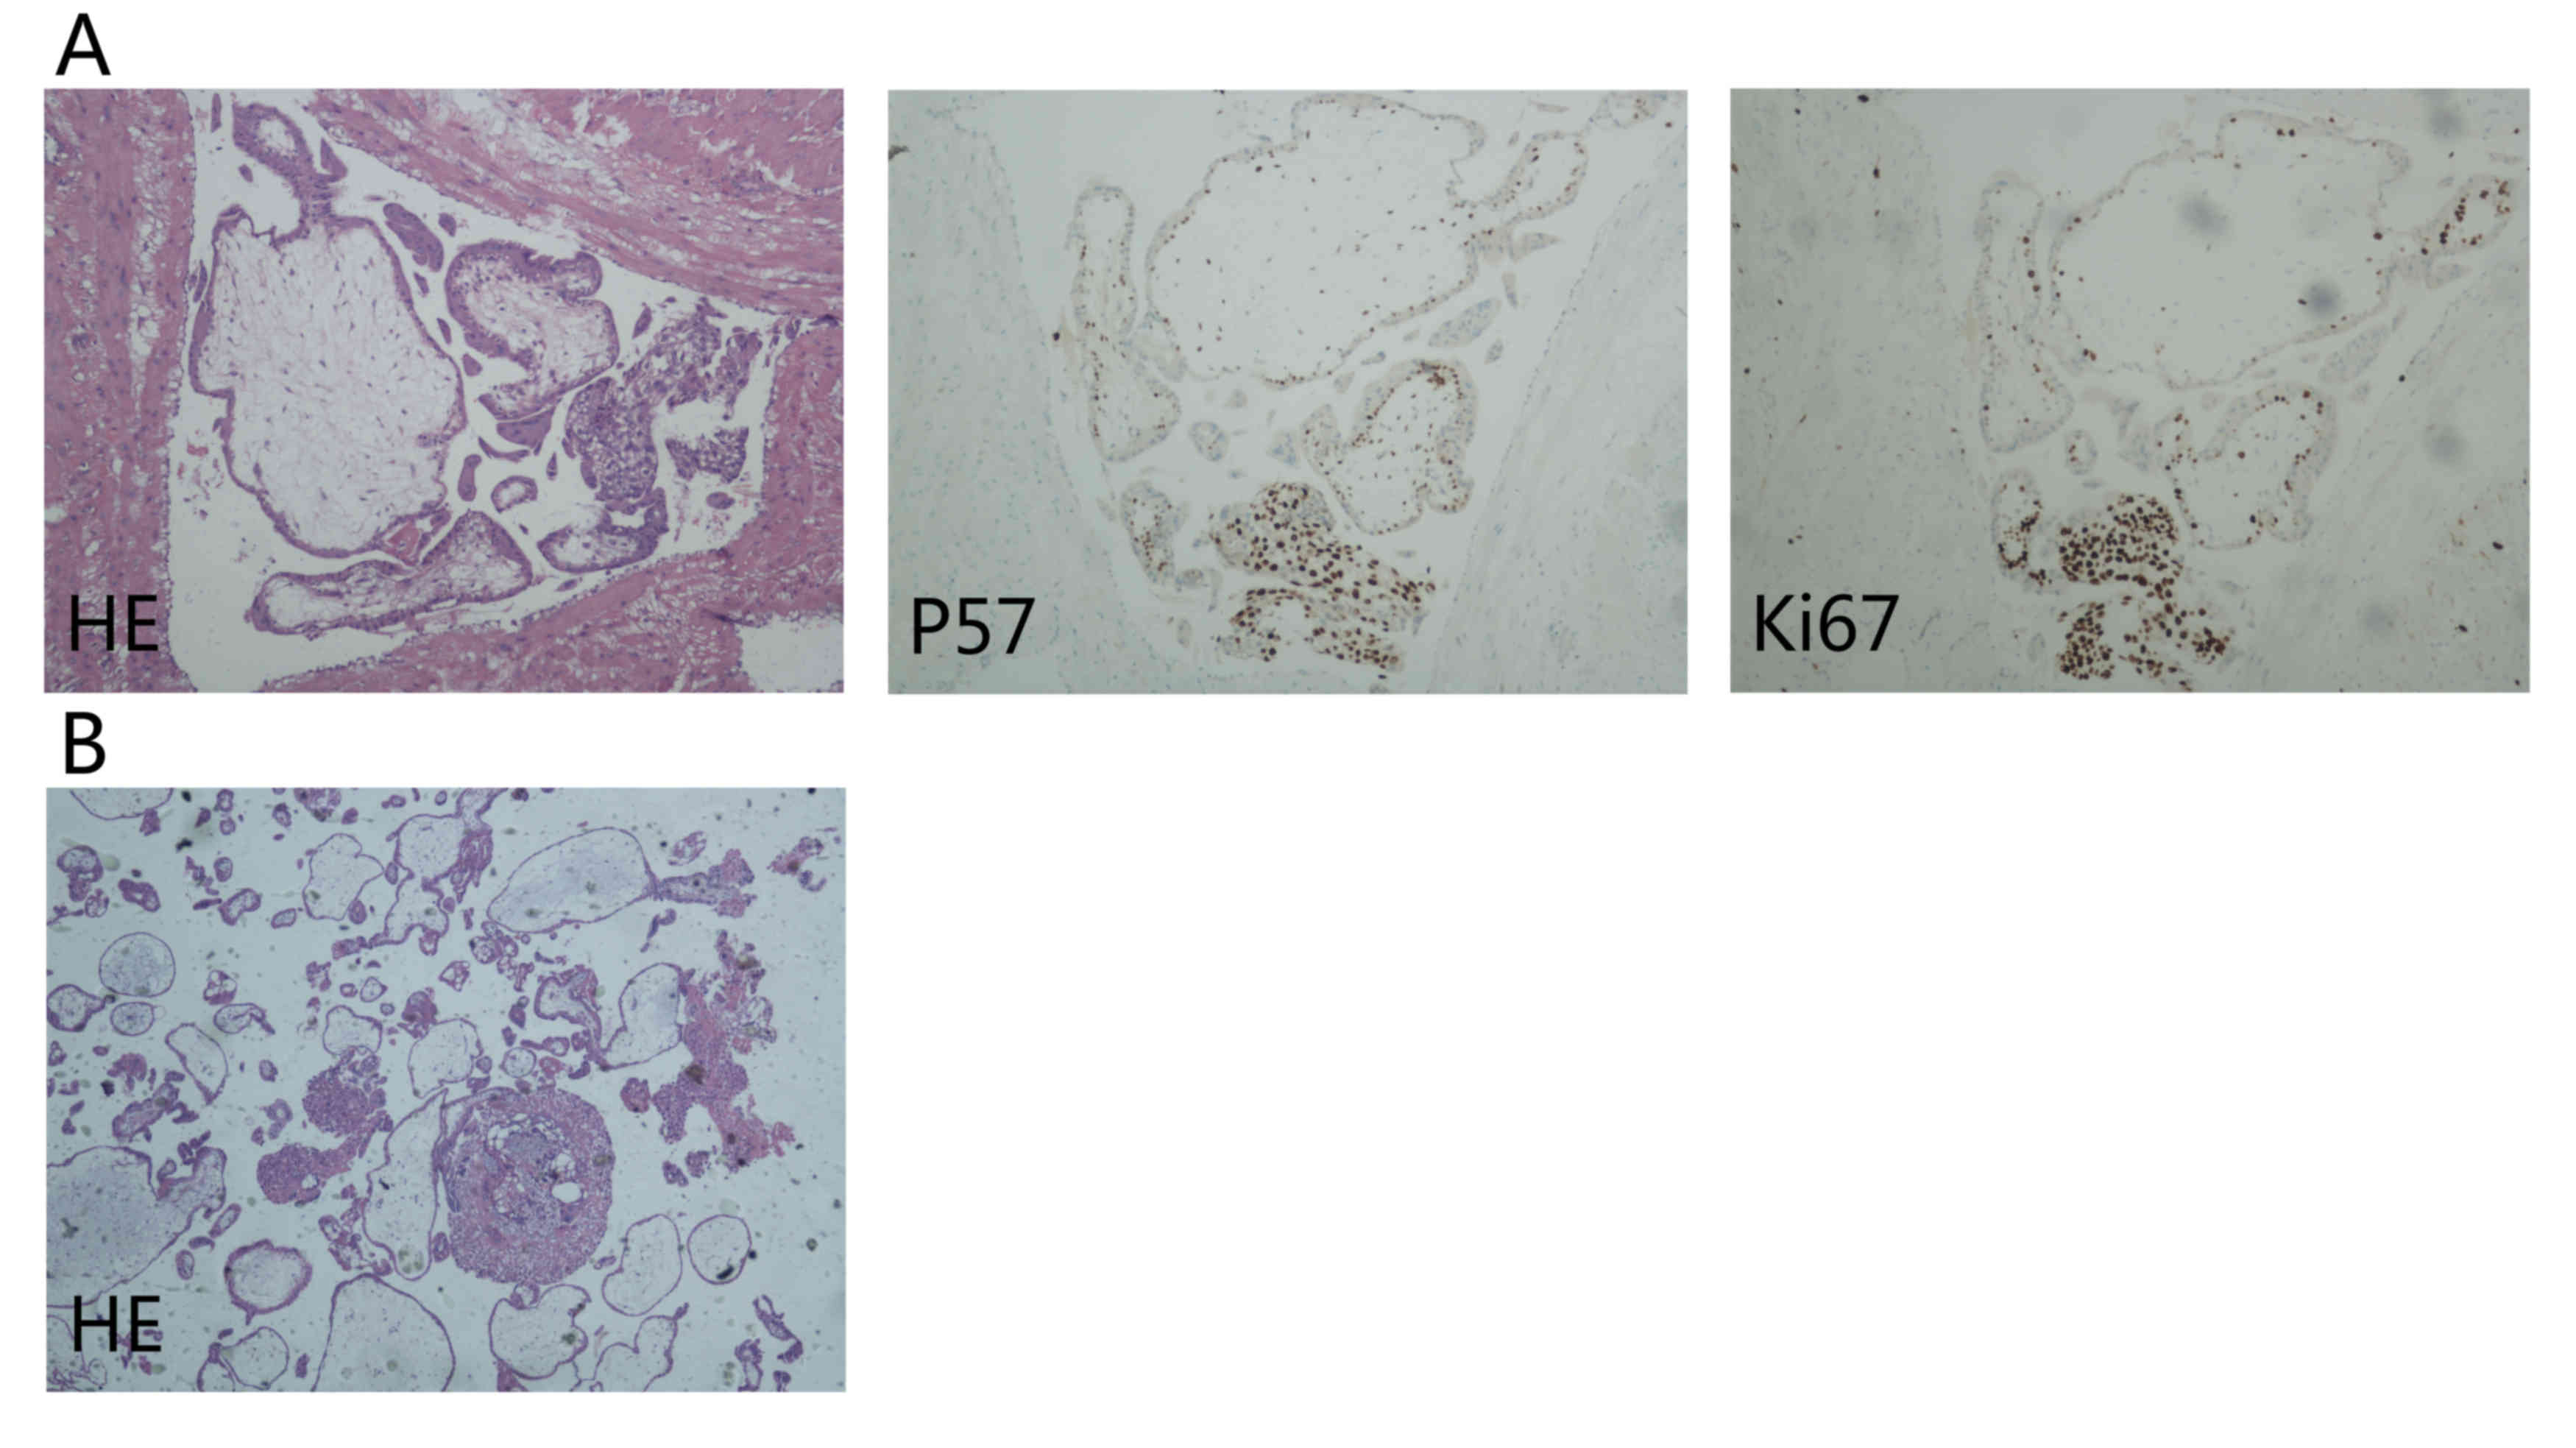

tissues were sent for routine pathological tests (Fig. 4).

Paraffin-embedded, 4-µm thick tissue sections from

the dissected tissues were stained with p57 and Ki-67 antibodies

for immunohistological analysis. All tissue sections were de-waxed,

rehydrated and incubated in 3% hydrogen peroxide for 10 min at room

temperature to halt endogenous peroxidase activity, then incubated

for 30–60 min with an anti-p57 antibody (Mouse Monoclonal Antibody;

ready-to-use dilution; cat. no., ZM-0252; ZSGB-BIO, Beijing, China)

and anti-Ki67 antibody (Rabbit Monoclonal Primary Antibody;

ready-to-use dilution, 2 ug/ml; cat. no., 790-4286; Roche

Diagnostics Shanghai Ltd., Shanghai, China) at room temperature.

Then the sections were incubated with a HRP-labeled staining

reagent (Universal Immuno-peroxidase Polymer Anti-Mouse/Rabbit

Immunohistochemical Staining reagent; ready-to-use dilution; cat.

no., PV-8000; ZSGB-BIO) at room temperature for 20 min. Sections

were developed with a DAB kit (ZSGB-BIO) used according to the

manufacturer's protocol. The tissue sections were washed 3 times

with phosphate-buffered saline (ZSGB-BIO) between each step.

Following staining, the tissue sections were counterstained using

hematoxylin (ZSGB-BIO), and subsequently dehydrated using ethanol

and xylene. Permount TM Mounting Medium (ZSGB-BIO) was then applied

to the coverslips. An ECLIPSE 80i research microscope (Nikon

Corporation, Tokyo, Japan) was used to observe the

immunohistological staining results at a magnification of

×40-x100.

Histological sections of the right rudimentary horn

revealed the myometrial invasion of massive placental villi and

metatypical trophoblastic cells (Fig.

4A). Immunohistological staining demonstrated positive

expression of p57, and a high Ki-67 proliferation index (Fig. 4A). Diagnostic curettage sections

showed the decidualized endometrium (Fig.

4B). Based on the high serum β-HCG level, imageological results

and the final pathology, the patient was diagnosed as follows:

invasive hydatidiform mole, rudimentary uterine horn and scarred